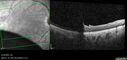

Paclitaxel induced cystoid macular edema - reversed when chemo stopped25 views74 year old retired physician About 2-3 weeks ago there was gradual vision loss in the right eye. The patient was seen by an ophthalmologist who saw macular swelling and injected vabysmo. He has been on chemotherapy (Carbiplatin and Carboxytaxol for 2 cancers - advanced prostrate diagnosed 2019 - has had brain surgery AND squamous lung cancers treated with radiation)

Medical Hx: Prostate cancer (Onset: 2018). Pulmonary and bone cancer metastatic. Brain cancer metastasized from prostate cancer.

Surgical Hx: Right frontal & Frontoparietal Craniotomy (Onset: 2024). Appendectomy. Hemorrhoidectomy. Herniorrhaphy. Prostate. Systemic Meds: Chemotherapy. Radiation. Eligard Every 3 Months 22.5 MG per 0.375 ML Prefilled Syringe. MIRALAX prn. Tums Freshers 500 MG Chewable Tablet. Vitamin D. XGEVA.

VA OD: Dcc20/125+1

VA OS: Dcc20/125-2

TP: OD:12 OS:15Aug 17, 2025